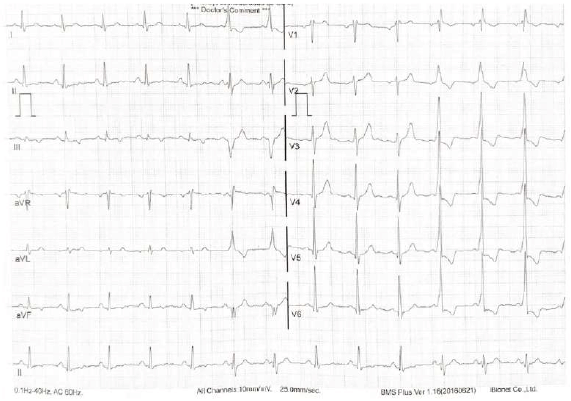

Homem de 78 anos, branco, apresenta quadro de dispneia progressiva aos esforços, atualmente em CF III, associado a edema de MMII. Ele refere que é hipertenso, atualmente com bom controle pressórico, em uso de anlodipino 2,5 mg 1x ao dia, e que se submeteu, há 5 anos, a uma cirurgia para síndrome do túnel do carpo bilateral. Seu pai faleceu em decorrência de cardiopatia aos 81 anos.

Ao exame físico, apresentou: PA 122x62 mmHg, FC 68 bpm, sem hipotensão ortostática, estase jugular presente a 45 graus, RCR com B4, sem sopro, edema de membros inferiores +/4+, sinal de Popeye (ruptura espontânea do bíceps braquial). Realizou o ecocardiograma, com mensuração do strain global longitudinal, reproduzido abaixo.

Considerando a hipótese mais provável, o próximo passo para a investigação diagnóstica, conforme o posicionamento da Sociedade Brasileira de Cardiologia de 2021, será